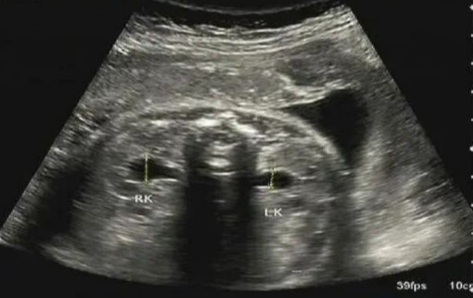

3.肾盂分离

1)是什么?胎儿肾脏的集合系统有轻度积液,导致肾盂前后径增宽。

2)意味着什么?可能是宝宝膀胱充盈时的一过性表现,也可能提示出生后存在肾积水或泌尿系统梗阻的风险。

3)怎么办?医生会根据分离的严重程度进行判断。轻度分离非常常见,大多在出生前后会自行吸收。只需定期B超随访观察其变化。如果持续加重,宝宝出生后需儿科随访。